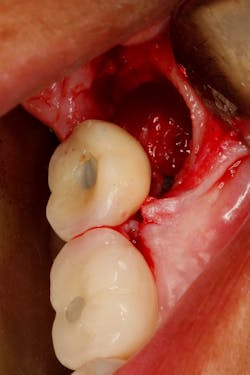

Late complications of bone augmentation are now recognized more frequently and include late resorption, foreign body reaction (figures 2a–2b), late breakdown of grafted sites (figures 3a–3e), lack of keratinized tissue and poor esthetics, as well as implant failure. While all bone augmentation procedures result in some degree of bone remodeling and resorption, significant late graft resorption can jeopardize the supporting bone around an already integrated implant, resulting in implant dehiscence, peri-implant disease, and late implant failure (figures 4a–4c). The degree of resorption depends on three important factors: alveolar defect configuration, patient factors, and the technique and grafting materials chosen.3

Figures 3a–3e: Socket preservation was performed at the site of the left mandibular second molar after extraction, using a biomaterial two years prior to implant placement. Six years after implant placement, sequestration of the biomaterial is seen, resulting in peri-implant infection and failure of the implant.